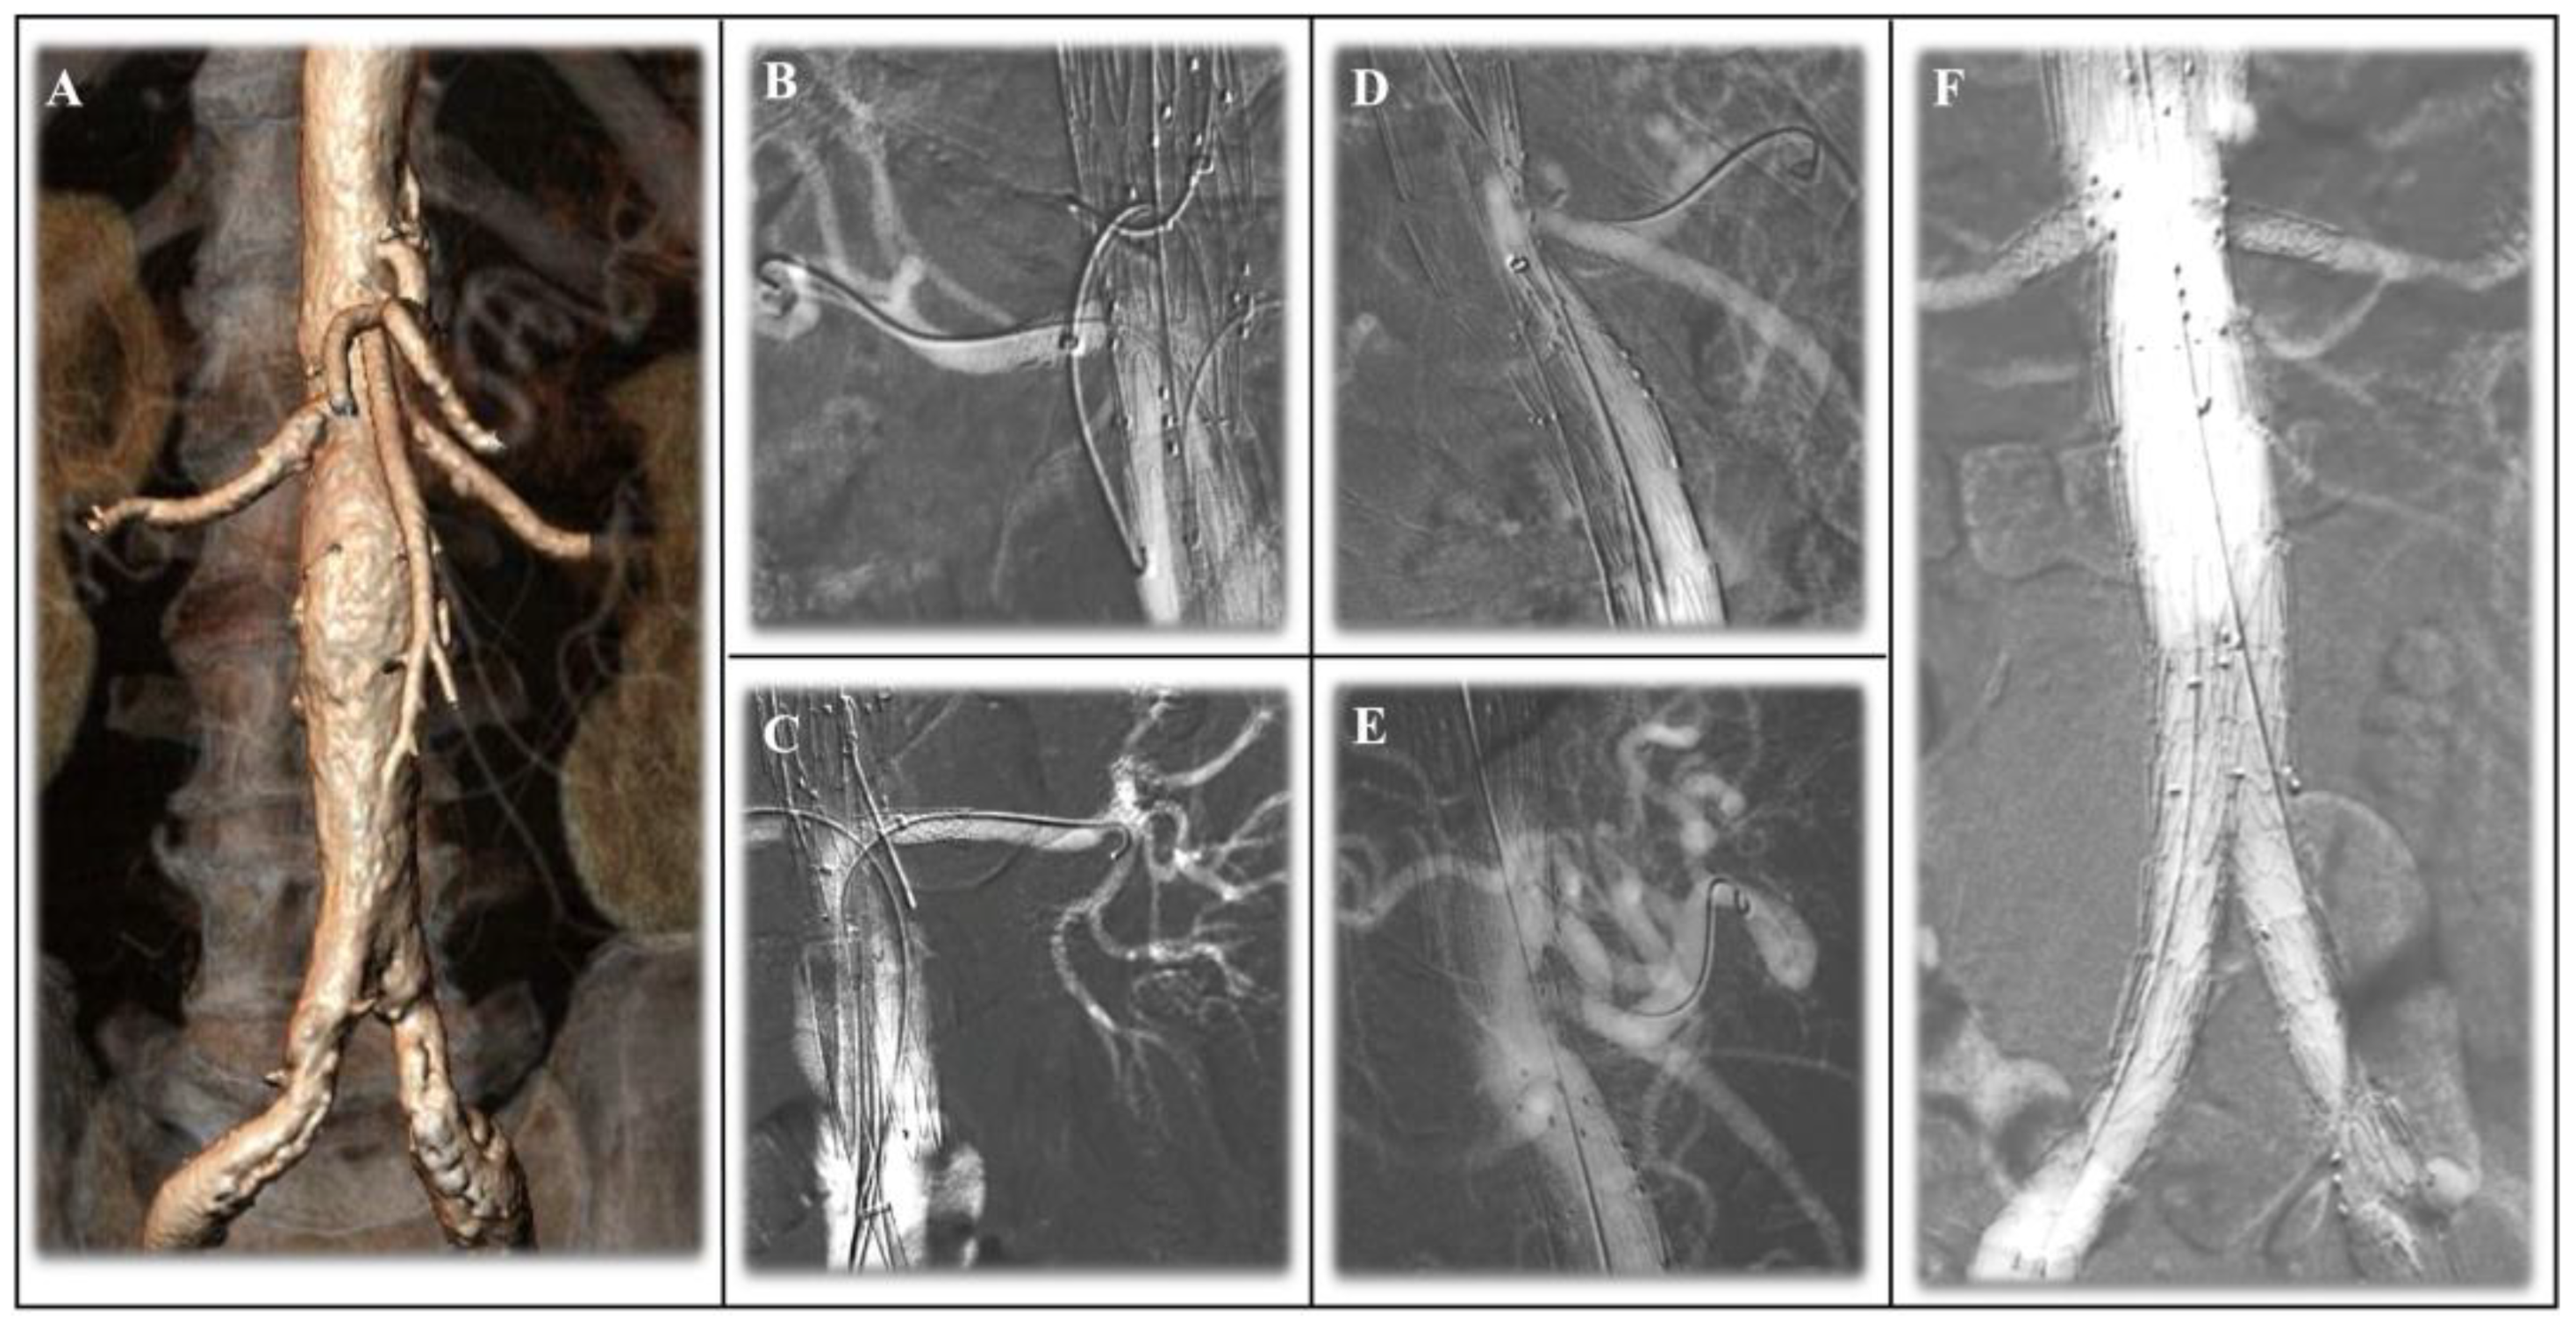

- Gallitto, E.; Faggioli, G.; Vacirca, A.; Pini, R.; Mascoli, C.; Fenelli, C.; Logiacco, A.; Abualhin, M.; Gargiulo, M. The Benefit of Combined Carbon Dioxide Automated Angiography and Fusion Imaging in Preserving Perioperative Renal Function in Fenestrated Endografting. J. Vasc. Surg. 2020, 72, 1906–1916. [Google Scholar] [CrossRef]

3.2. CO2-DSA in Fenestrated and Branched EVAR: Techniques and Search of the Literature